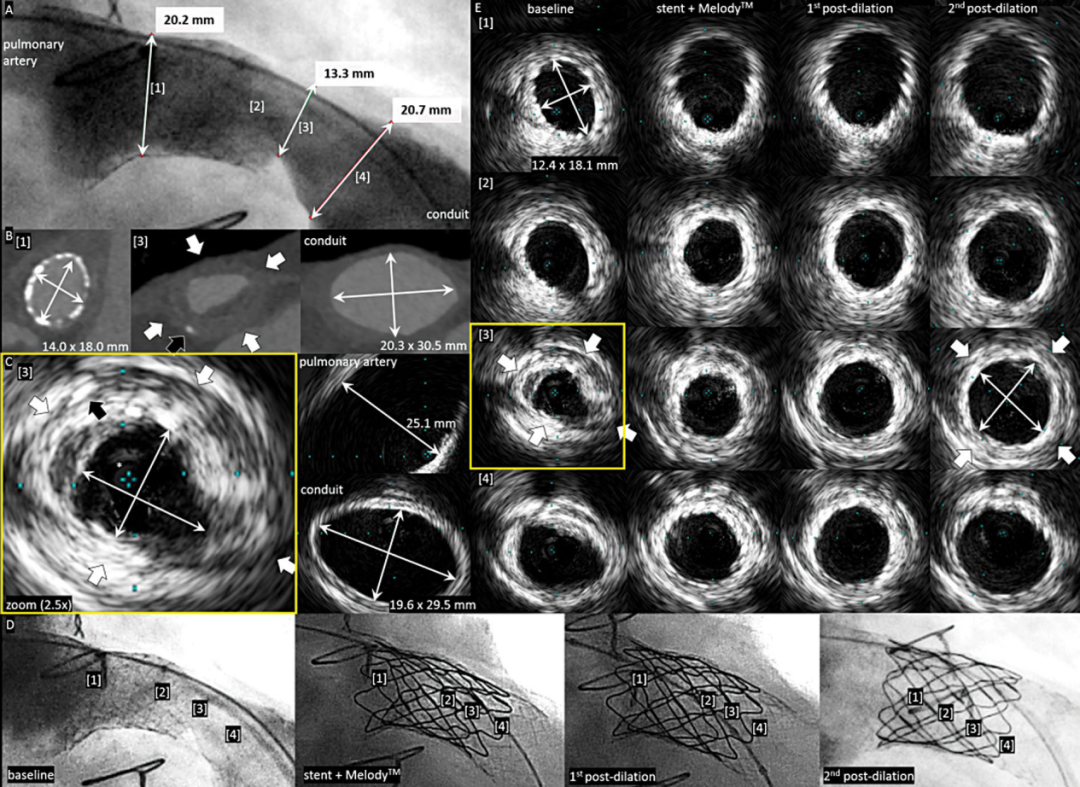

术前右心室测压84/0-21mmHg,血管造影显示支架近端肺动脉狭窄程度34%,CT显示肺动脉最窄处位于肺动脉环支架近端边缘。术中通过IVUS准确测量肺动脉及支架尺寸,提示最窄处肺动脉横截面积0.97cm2。在原支架近端植入Melody肺动脉瓣并充分覆盖至支架远端,球囊加压扩张后造影结果提示瓣膜扩张贴合良好,然而,IVUS测量最窄处面积仅1.58cm²,再次进行两次更高压力球囊加压扩张,最终IVUS测量原狭窄处横截面积达3.16cm²,右心室压降至37/0-4mmHg。